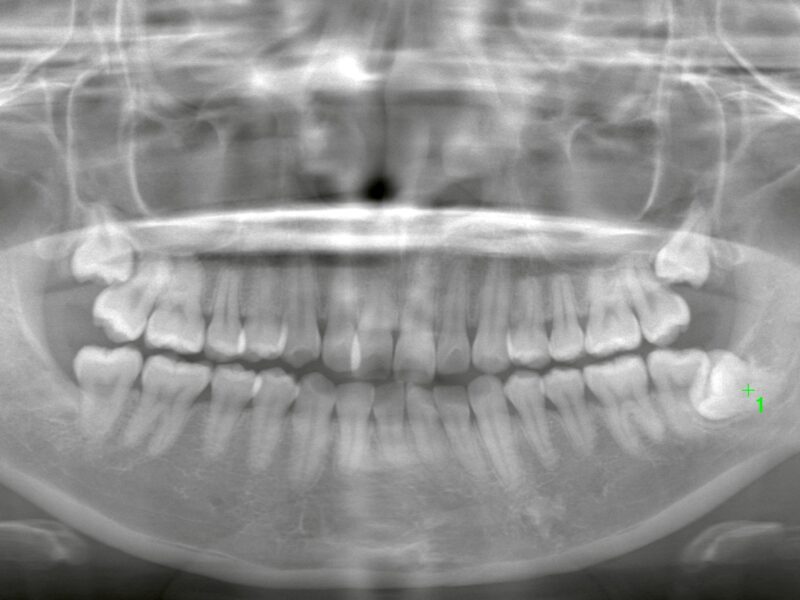

特徴4高精度診断を可能にする「歯科用CT」 -